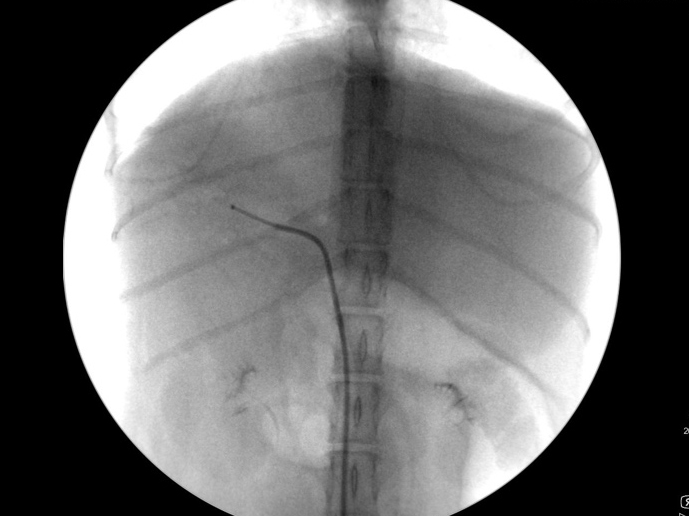

手術中の様子